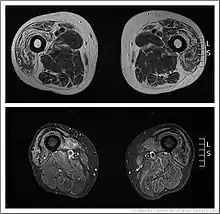

Bilateral medial forearm and quadriceps wasting of inclusion body myositis (rimmed vacuole within a muscle fibre histopathologically -

Affected quadriceps (rectus femoris) in IBM -